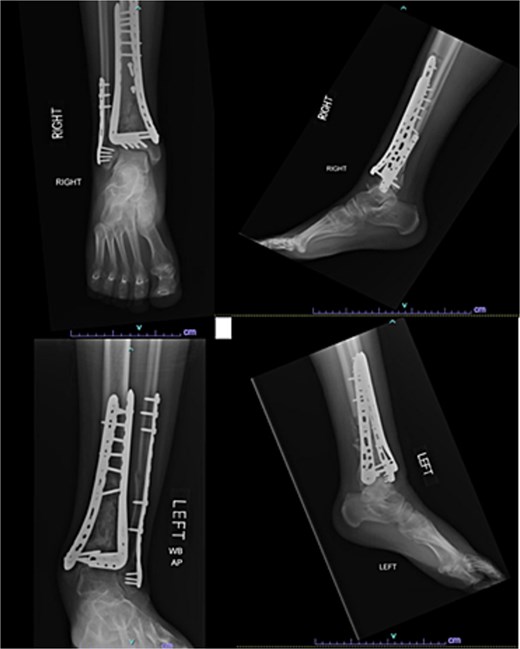

One year after the initial surgery, the left leg healed without any complications. However, the right leg developed nonunion through the distal tibia, along with posttraumatic arthritis. As a result, the patient underwent a right ankle fusion. Additionally, 2.5 years after the index surgery (1.5 years after the ankle fusion), the patient required removal of the right lateral fibular plate due to painful hardware. Six months later (3 years post-index surgery), the patient then underwent subtalar fusion due to post-traumatic arthropathy and ongoing pain (Fig. 2).

Radiographs of patient 1 obtained 3 years after the index procedure, including AP view of the left ankle and lateral and oblique views of the right ankle following subtalar fusion.